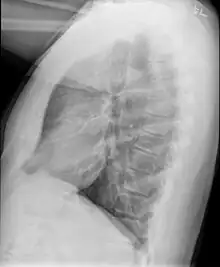

Example of early disease with mild flattening of the diaphram

Obliterative bronchiolitis is often diagnosed based on the symptoms of obstructive lung disease following lung injury. The definitive diagnosis is through biopsy, but due to the variable distribution of lesions, leading to falsely negative tests, and invasive nature of this procedure it is often not performed.[6][11] Several tests are often needed to diagnose obliterative bronchiolitis, including spirometry, diffusing capacity of the lung tests (DLCO), lung volume tests, chest X-rays, high-resolution CT (HRCT), and lung biopsy.[11][4]

Early in the disease chest radiography is typically normal but may show hyperinflation.[6] As the disease progresses a reticular pattern with thickening of airway walls may be present.[4][6] HRCT can also show air trapping when the person being scanned breathes out completely; it can also show thickening in the airway and haziness in the lungs.[11] A common finding on HRCT is patchy areas of decreased lung density, signifying reduced vascular caliber and air trapping.[6] This pattern is often described as a "mosaic pattern", and may indicate obliterative bronchiolitis.[6]